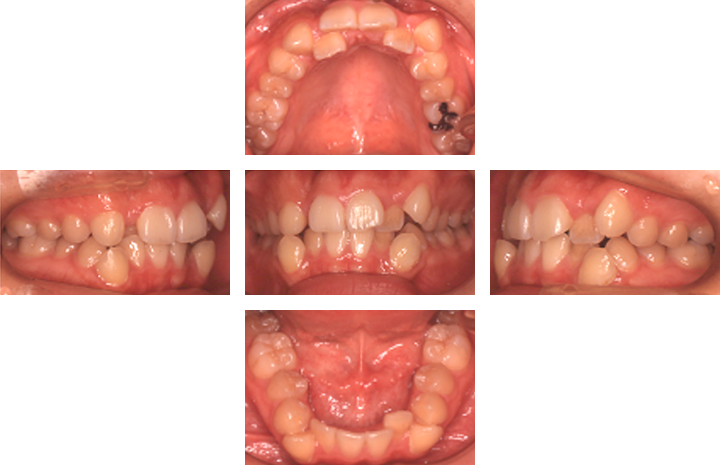

治療後

叢生case2. 10代女性(治療期間1年11か月)

| 主訴 | ①歯並びが悪い(審美障害)②歯みがきがしづらい |

|---|---|

| 診断名 | 叢生、前歯部交叉咬合 |

| 初診時年齢 | 17歳8か月 |

| 性別 | 女性 |

| 動的治療期間 | 1年11か月 |

| 主な矯正装置 | マルチブラケット装置、リンガルアーチ |

| 抜歯/非抜歯 | 上下顎両側4番 |

| 治療費用(税込) | 検査診断:44,000円 装置料:440,000円 調節料:5,500円×21回 |

| 副作用とリスク | マルチブラケット装置は歯みがきが難しく、むし歯や歯肉炎になりやすい。歯を動かすと歯根が短くなることがある。 |

治療前